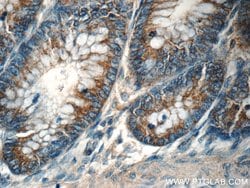

| Immunohistochemistry (Paraffin), Western Blot | |